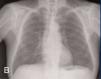

The first relapse of the disease was found two years and 3 months after the ANCA had become positive and while the patient was undergoing immunosuppressive treatment with oral cyclophosphamide at 50mg/day. The patient had anti-MPO at a titre of 367U/ml and the relapse appeared as acute non-oliguric renal failure (creatinine peak at a maximum of 6.6mg/dl), microscopic haematuria and pulmonary haemorrhage in the right lung (Figure 1) that responded to treatment with 500mg pulses of 6-methylprednisone i.v. (three doses) followed by oral prednisone at 1mg/kg/day and 500g pulses of cyclophosphamide. Two months after this first relapse, the patient was admitted to hospital for another respiratory infection without pulmonary consolidation that responded well to levofloxacin.

Figure 1a. Pulmonary haemorrhage in the right hemithorax (A) before treatment and (B) after receiving immunosuppressive treatment.

Figure 1b. Pulmonary haemorrhage in the right hemithorax (A) before treatment and (B) after receiving immunosuppressive treatment.